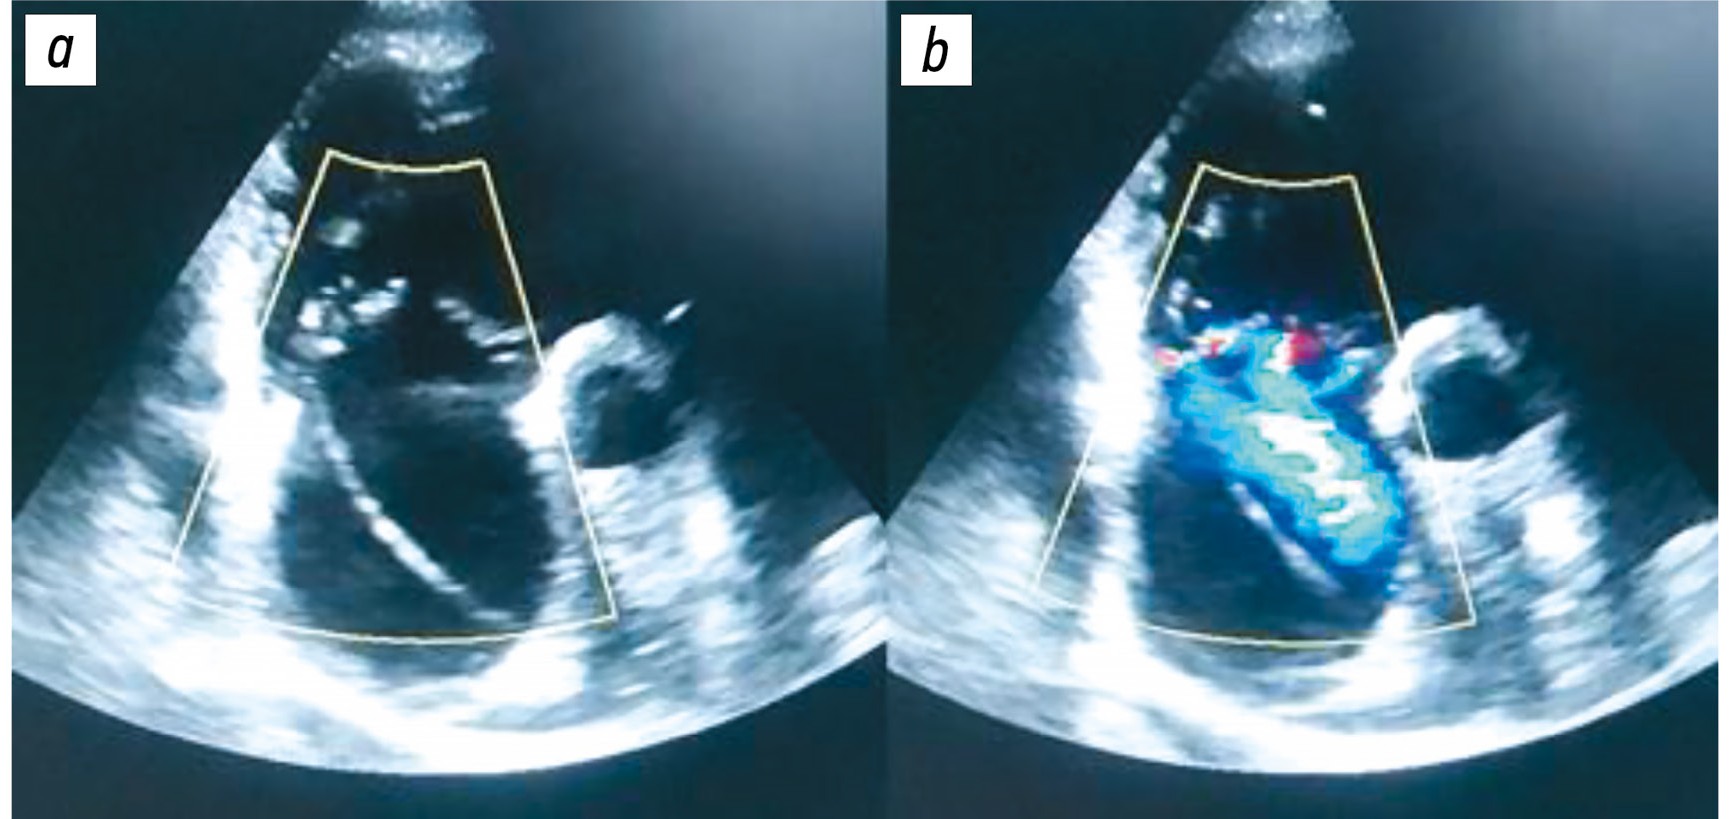

Через 3 мес. после имплантации пациент поступил в стационар с жалобами на нарастание периферических отёков и увеличение живота в объёме. Концентрация N-терминального пропептида натрийуретического гормона при поступлении составила 6000 пг/мл. Рентгенография органов грудной клетки выявила кардиомегалию и признаки венозного застоя. По данным ультразвукового исследования брюшной полости обнаружено умеренное количество жидкости в брюшной полости. На эхокардиограмме отмечена дилатация обоих предсердий, выявлена умеренная митральная и тяжёлая ТР, градиент на ТК составил 25 мм рт. ст. При фокусной визуализации правых камер сердца выявлены признаки перфорации створки ТК электродом ЭКС (рис. 1).

Рис. 1. Трансторакальная эхокардиография: a — перфорация передней створки трикуспидального клапана желудочковым электродом электрокардиостимулятора; b — цветовое допплеровское картирование: струя регургитации, проходящая сквозь отверстие перфорации.

Прослеживалась чёткая причинно-следственная связь между имплантацией ЭКС и ухудшением клинического состояния, а также декомпенсацией хронической сердечной недостаточности. Именно после установки устройства было отмечено прогрессирование правожелудочковой недостаточности с отёками нижних конечностей и небольшим асцитом. ЭхоКГ позволила заподозрить непосредственный механизм — повреждение створки ТК электродом. Своевременное распознавание этого осложнения стало отправной точкой для пересмотра тактики ведения пациента и обсуждения вопроса о хирургической коррекции.